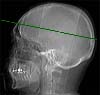

Radioanatomie TDM de l'encéphale avec injection